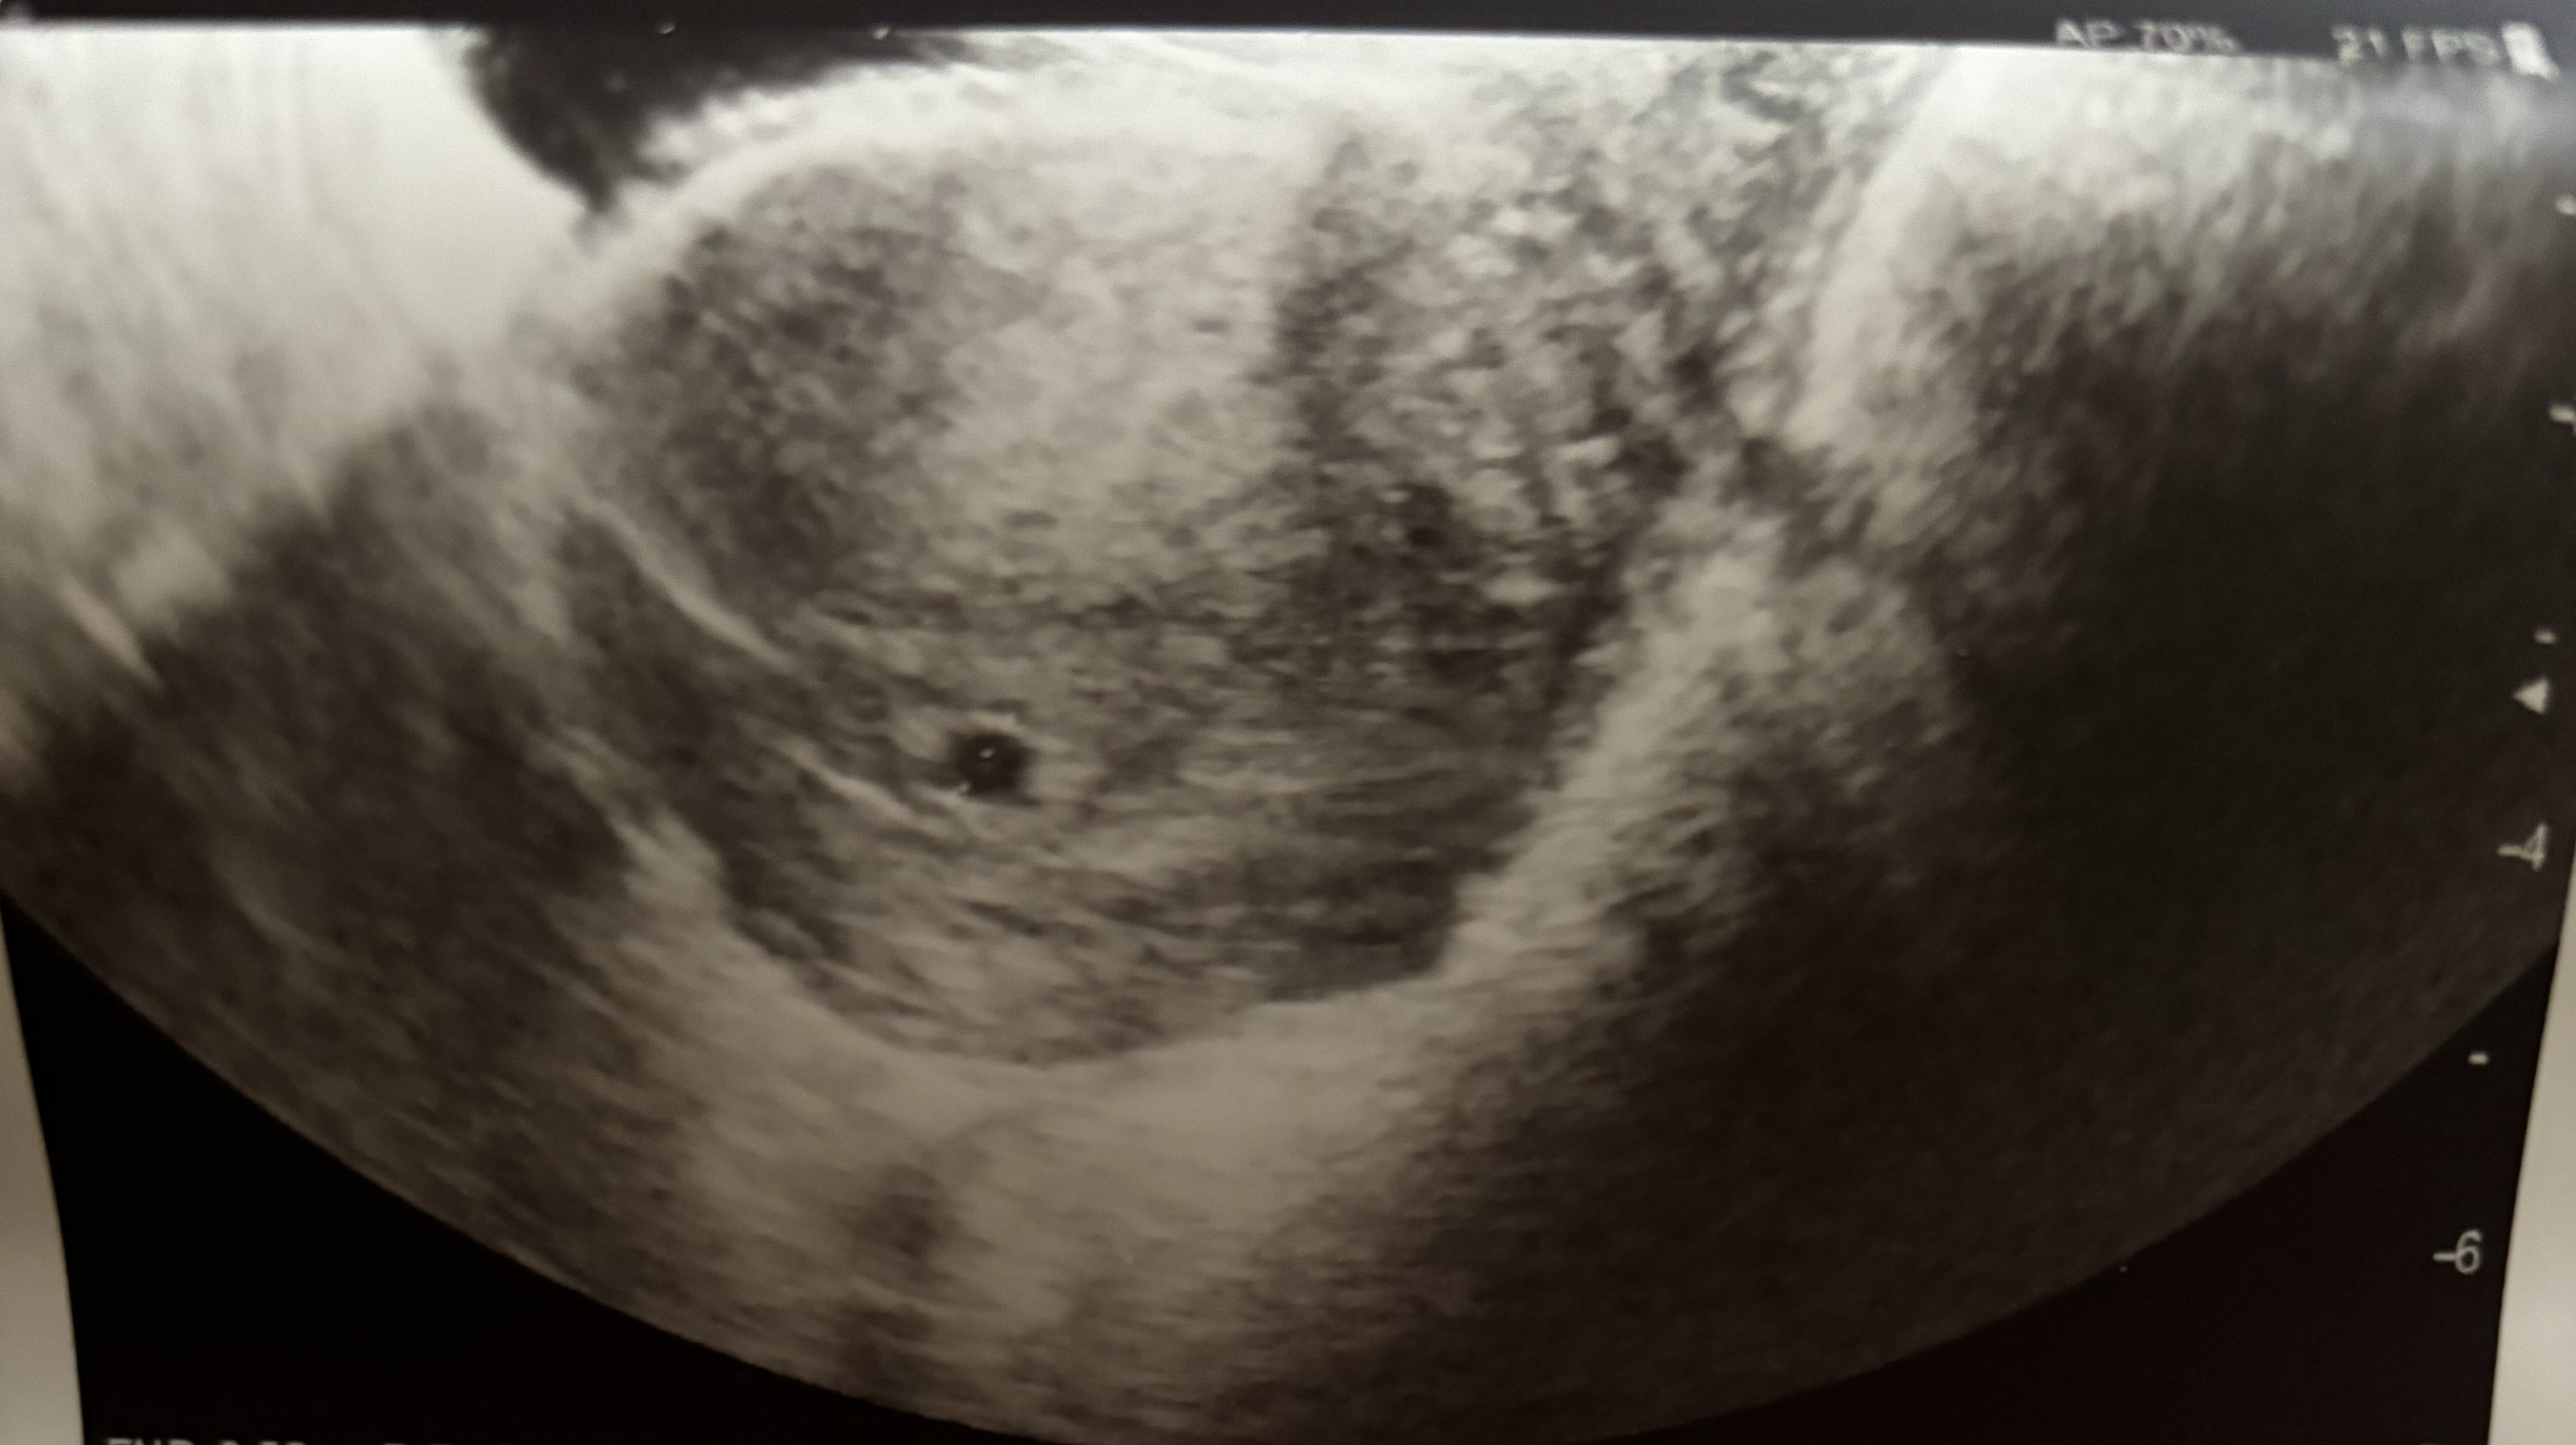

Jestem już po wizycie, jestem w 5 tygodniu, jest pęcherzyk ciążowy, mam wizytę za 2 tygodnie. ( dostałam zwolnienie do czasu następnej wizyty ze względu na krwawienie)

Załączniki

• IMG_7490.jpeg

IMG_7490.jpeg

1,1 MB · Wyświetleń: 112

Widzę, że u gina już byłaś i pęcherzyk widać.

Serduszko za te 2 tygodnie przy następnej wizycie też spokojnie powinno już być.